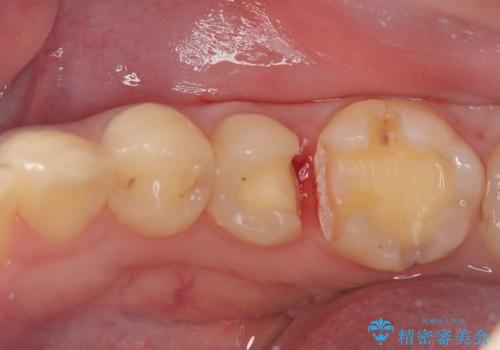

- 主訴:銀の詰め物が取れた、奥の銀の詰め物も一緒に白くしたい

保険適用のメタルインレーの脱離で来院されました。審美性、適合性、清掃性の観点から2本ともセラミックインレーでのやり替えとなりました。

保険適用のメタルインレーはセラミックやゴールドに比べるとプラークなどの汚れが付きやすく、また今回はそこまで大きなう蝕は広がっていませんでしたが、適合性に限界があるためインレーと歯質との境目で二次う蝕が発生する可能性が高くなります。